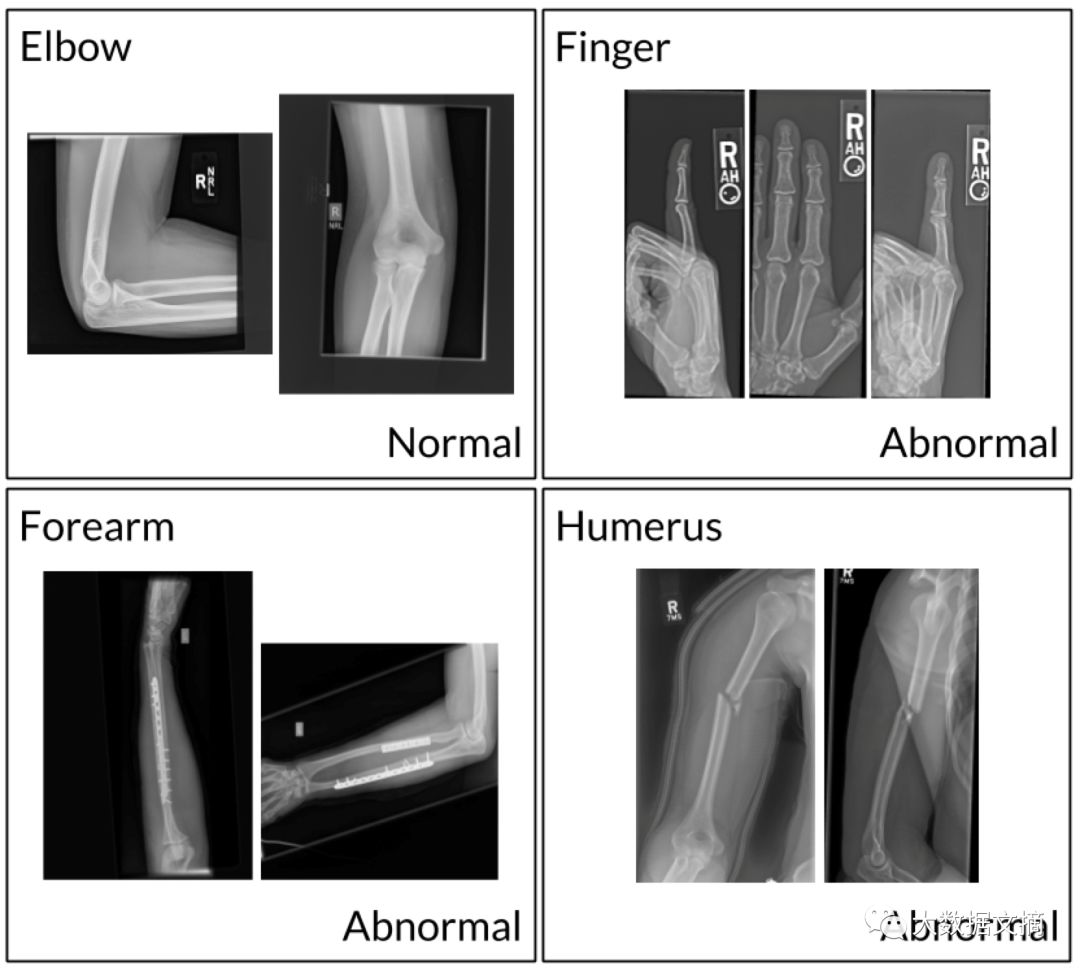

目前,肌肉骨骼疾病影响全球超过17亿人,斯坦福这一数据集旨在帮助医学影像技术取得重大进展,从而改善世界上许多缺乏放射科医生的医疗机构的状况。 据官网介绍,MURA是肌肉骨骼放射照片的数据集,由来自12,173名患者的14,863项研究组成,总共包含40,561个多视角放射图像。 图片囊括了七种放射科主要研究对象:手肘,手指,前臂,手,肱骨,肩膀和手腕。